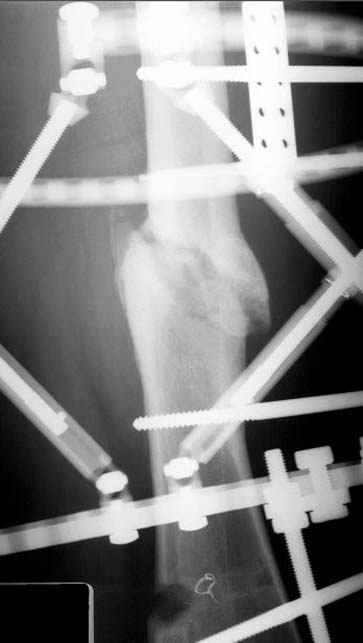

Несколько снимков из моей коллекции, чтобы разьяснить, почему мы до сих пор делаем различные варианты остеотомии.

N3 рисунок окончательный снимок, после операции моя рентгенограмма должен выглядеть примерно как эта картина. На N4 снимке клин перед удалением; N5 послеоперации 3 нед.; N6 окончательная рентгенограмма.

Отправитель: Djoldas Kuldjanov 23 Ноябрь 2004, 18:21

пластическая модель; и коррекция бедра аппаратом Илизарова.

• Re: Hip joint

Отправитель: Alexander Chelnokov 23 Ноябрь 2004, 21:29

Попробую угадать - была инфекция?

Отправитель: Evgueny Tschekashkin 24 Ноябрь 2004, 21:09

хотя даже если бы и инфекция , то nail exchange с рассверливанием канала - вариант дебрайдмента) Я думаю, что последовательность развития событий:

Узкий к-м канал - тонкий гвоздь- усталостный перелом дистальных винтов - развитие нестабильности и как ее результат остеолиз вокруг гвоздя - деформация анатомической оси бедра. Похоже, что я понял почему аппарат, а не новый гвоздь:-)